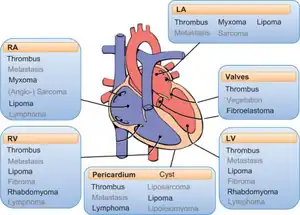

A cardiac myxoma is a noncancerous tumor of the heart that may embolise and grow at the site of embolisation.[1] Symptoms depend on the tumor size, location, shape, mobility and how fast it grows.[1] More than two-thirds have severe symptoms such as heart failure, stroke and embolisation.[3] Up to a fifth may have no symptoms.[1] Typical presentations include shortness of breath, feeling faint, chest pain, palpitations, fever, weight loss and joint pains.[1] There may be sudden death.[1]

Although any chamber may be affected, most arise within the left atrium near the valve of the fossa ovalis.[1] It may run in families as part of Carney syndrome, or may occur sporadically.[2] The tumor is derived from multipotent mesenchymal cells.[4]

Myxomata are the most common type of adult primary heart tumor.[4] [8] Most myxomata arise sporadically (90%), and only about 10% are thought to arise due to inheritance.[9]

About 10% of myxomata are inherited, as in Carney syndrome. Such tumors are called familial myxomata. They tend to occur in more than one part of the heart at a time, and often cause symptoms at a younger age than other myxomata. Other abnormalities are observed in people with Carney syndrome include skin myxomata, pigmentation, endocrine hyperactivity, schwannomas and epithelioid blue nevi.[4] Myxomata are more common in women than men.[4][6]

Right atrial myxomata rarely produce symptoms until they have grown to be at least 13 cm (about 5 inches) wide.